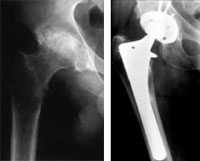

X-ray of hip with rheumatoid arthritis and total hip replacement

Reproduced with permission from Lachiewicz PF: Rheumatoid Arthritis of the Hip. J Am Acad Orthop Surg 1997; 5: 332-338.